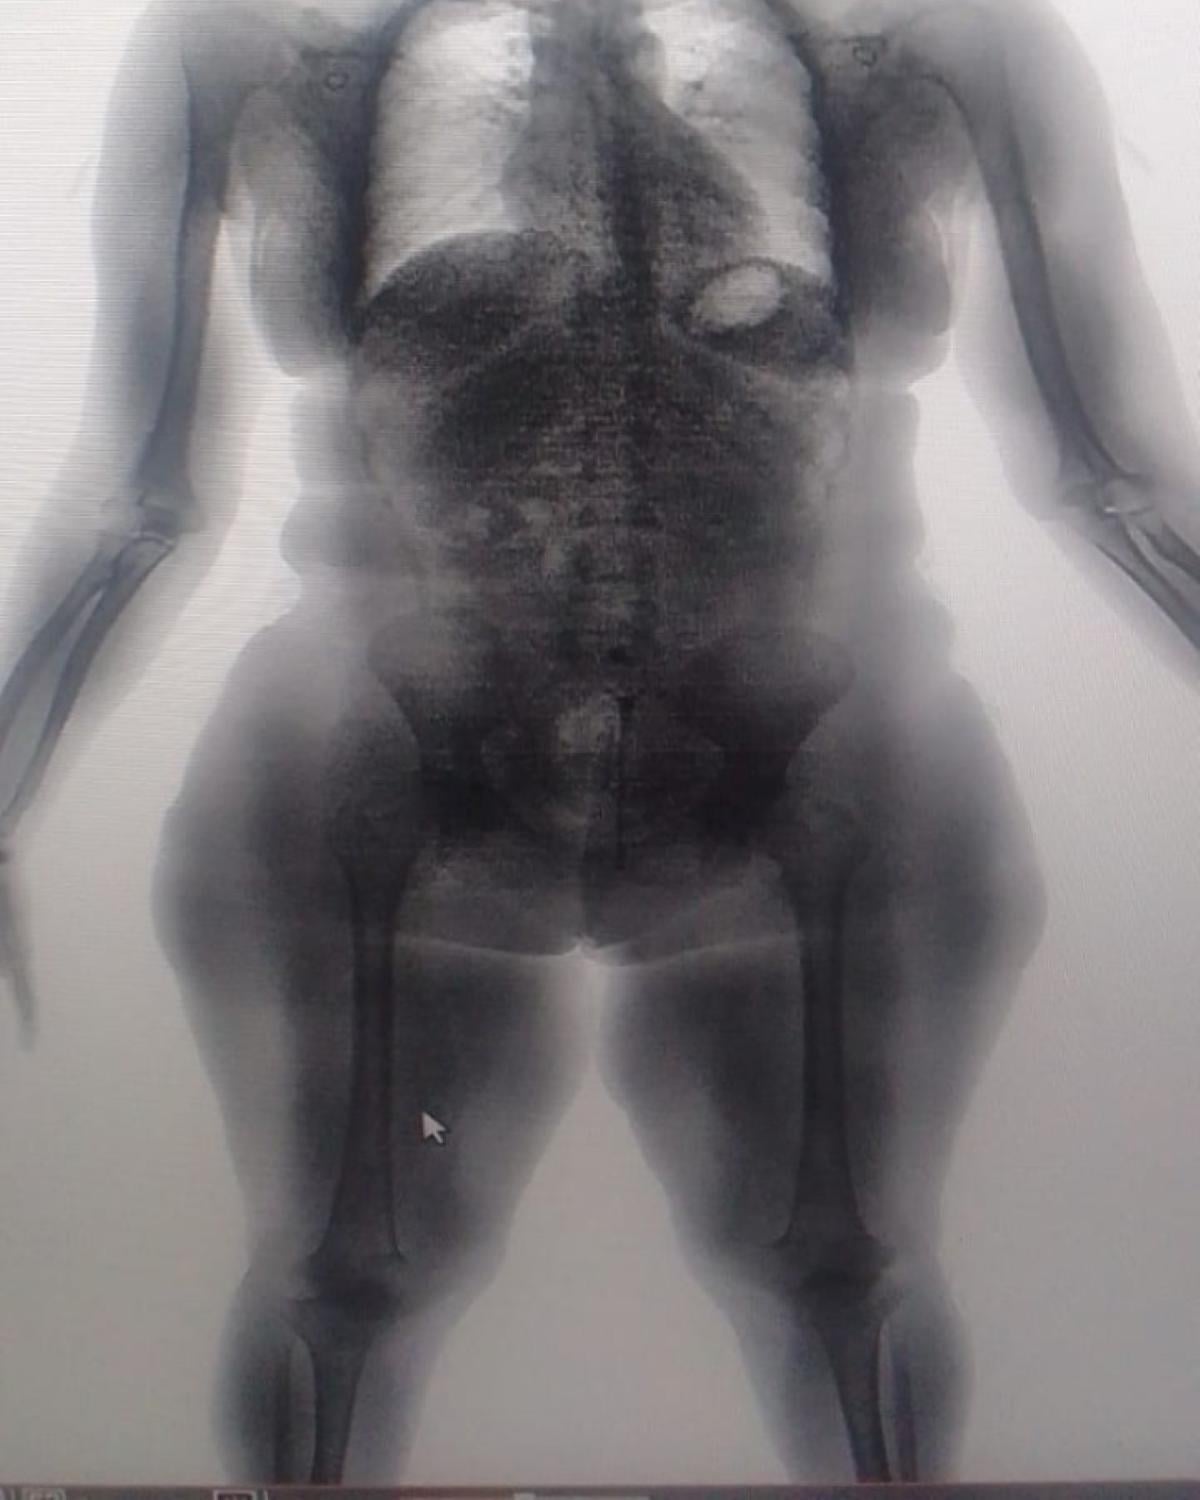

O caso aconteceu na quinta-feira (18), no Conjunto Penal de Lauro de Freitas, quando uma visitante foi flagrada pelas imagens do BodyScan, o scanner corporal usado nas revistas padrão das unidades prisionais do estado, com substâncias análogas à maconha e à cocaína em seu corpo. A mulher havia tentado burlar o mecanismo de revista introduzindo o material em suas partes íntimas.

O fato foi devidamente registrado por meio de Comunicado de Evento, sendo a visitante conduzida à 27ª DT – Delegacia Territorial de Itinga/Lauro de Freitas para adoção das medidas cabíveis previstas em lei. O material ilícito, cerca de 96 gramas, foi apreendido e, em seguida, adotadas as providências.

No mesmo dia, mas no Conjunto Penal de Eunápolis, sete visitantes foram detidas ao tentar entrar com drogas escondidas em uma espécie de compartimento secreto nas sandálias. Uma delas ainda tentou esconder as substâncias em seu corpo, introduzindo-as nas partes íntimas. A tentativa de burlar o sistema também foi frustrada pelo preparo dos agentes e pelas imagens do BodyScan.